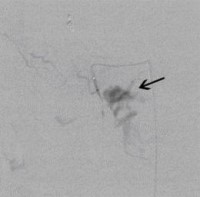

Postoperative abdominelle Blutungen bei chronischer Pankreatitis (Pfeile: Art. hepatica und Art. gastroduodenalis).

(Bild 1 von 5)

Postoperative abdominelle Blutungen bei chronischer Pankreatitis vor Embolisation der Art. gastroduodenalis mittels Metallspiralen (Coils)

(Bild 2 von 5)

Postoperative abdominelle Blutungen bei chronischer Pankreatitis nach Embolisation der Art. gastroduodenalis mittels Metallspiralen (Coils)

(Bild 3 von 5)